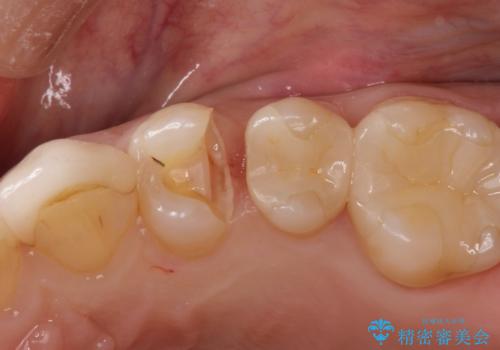

虫歯の治療(セラミックインレー)

- 定期検診にて虫歯が見つかり、セラミックインレーにて修復しております。

e-max プレスインレーにて修復治療を行っているため適合性及び審美性の高い治療を行うことができます